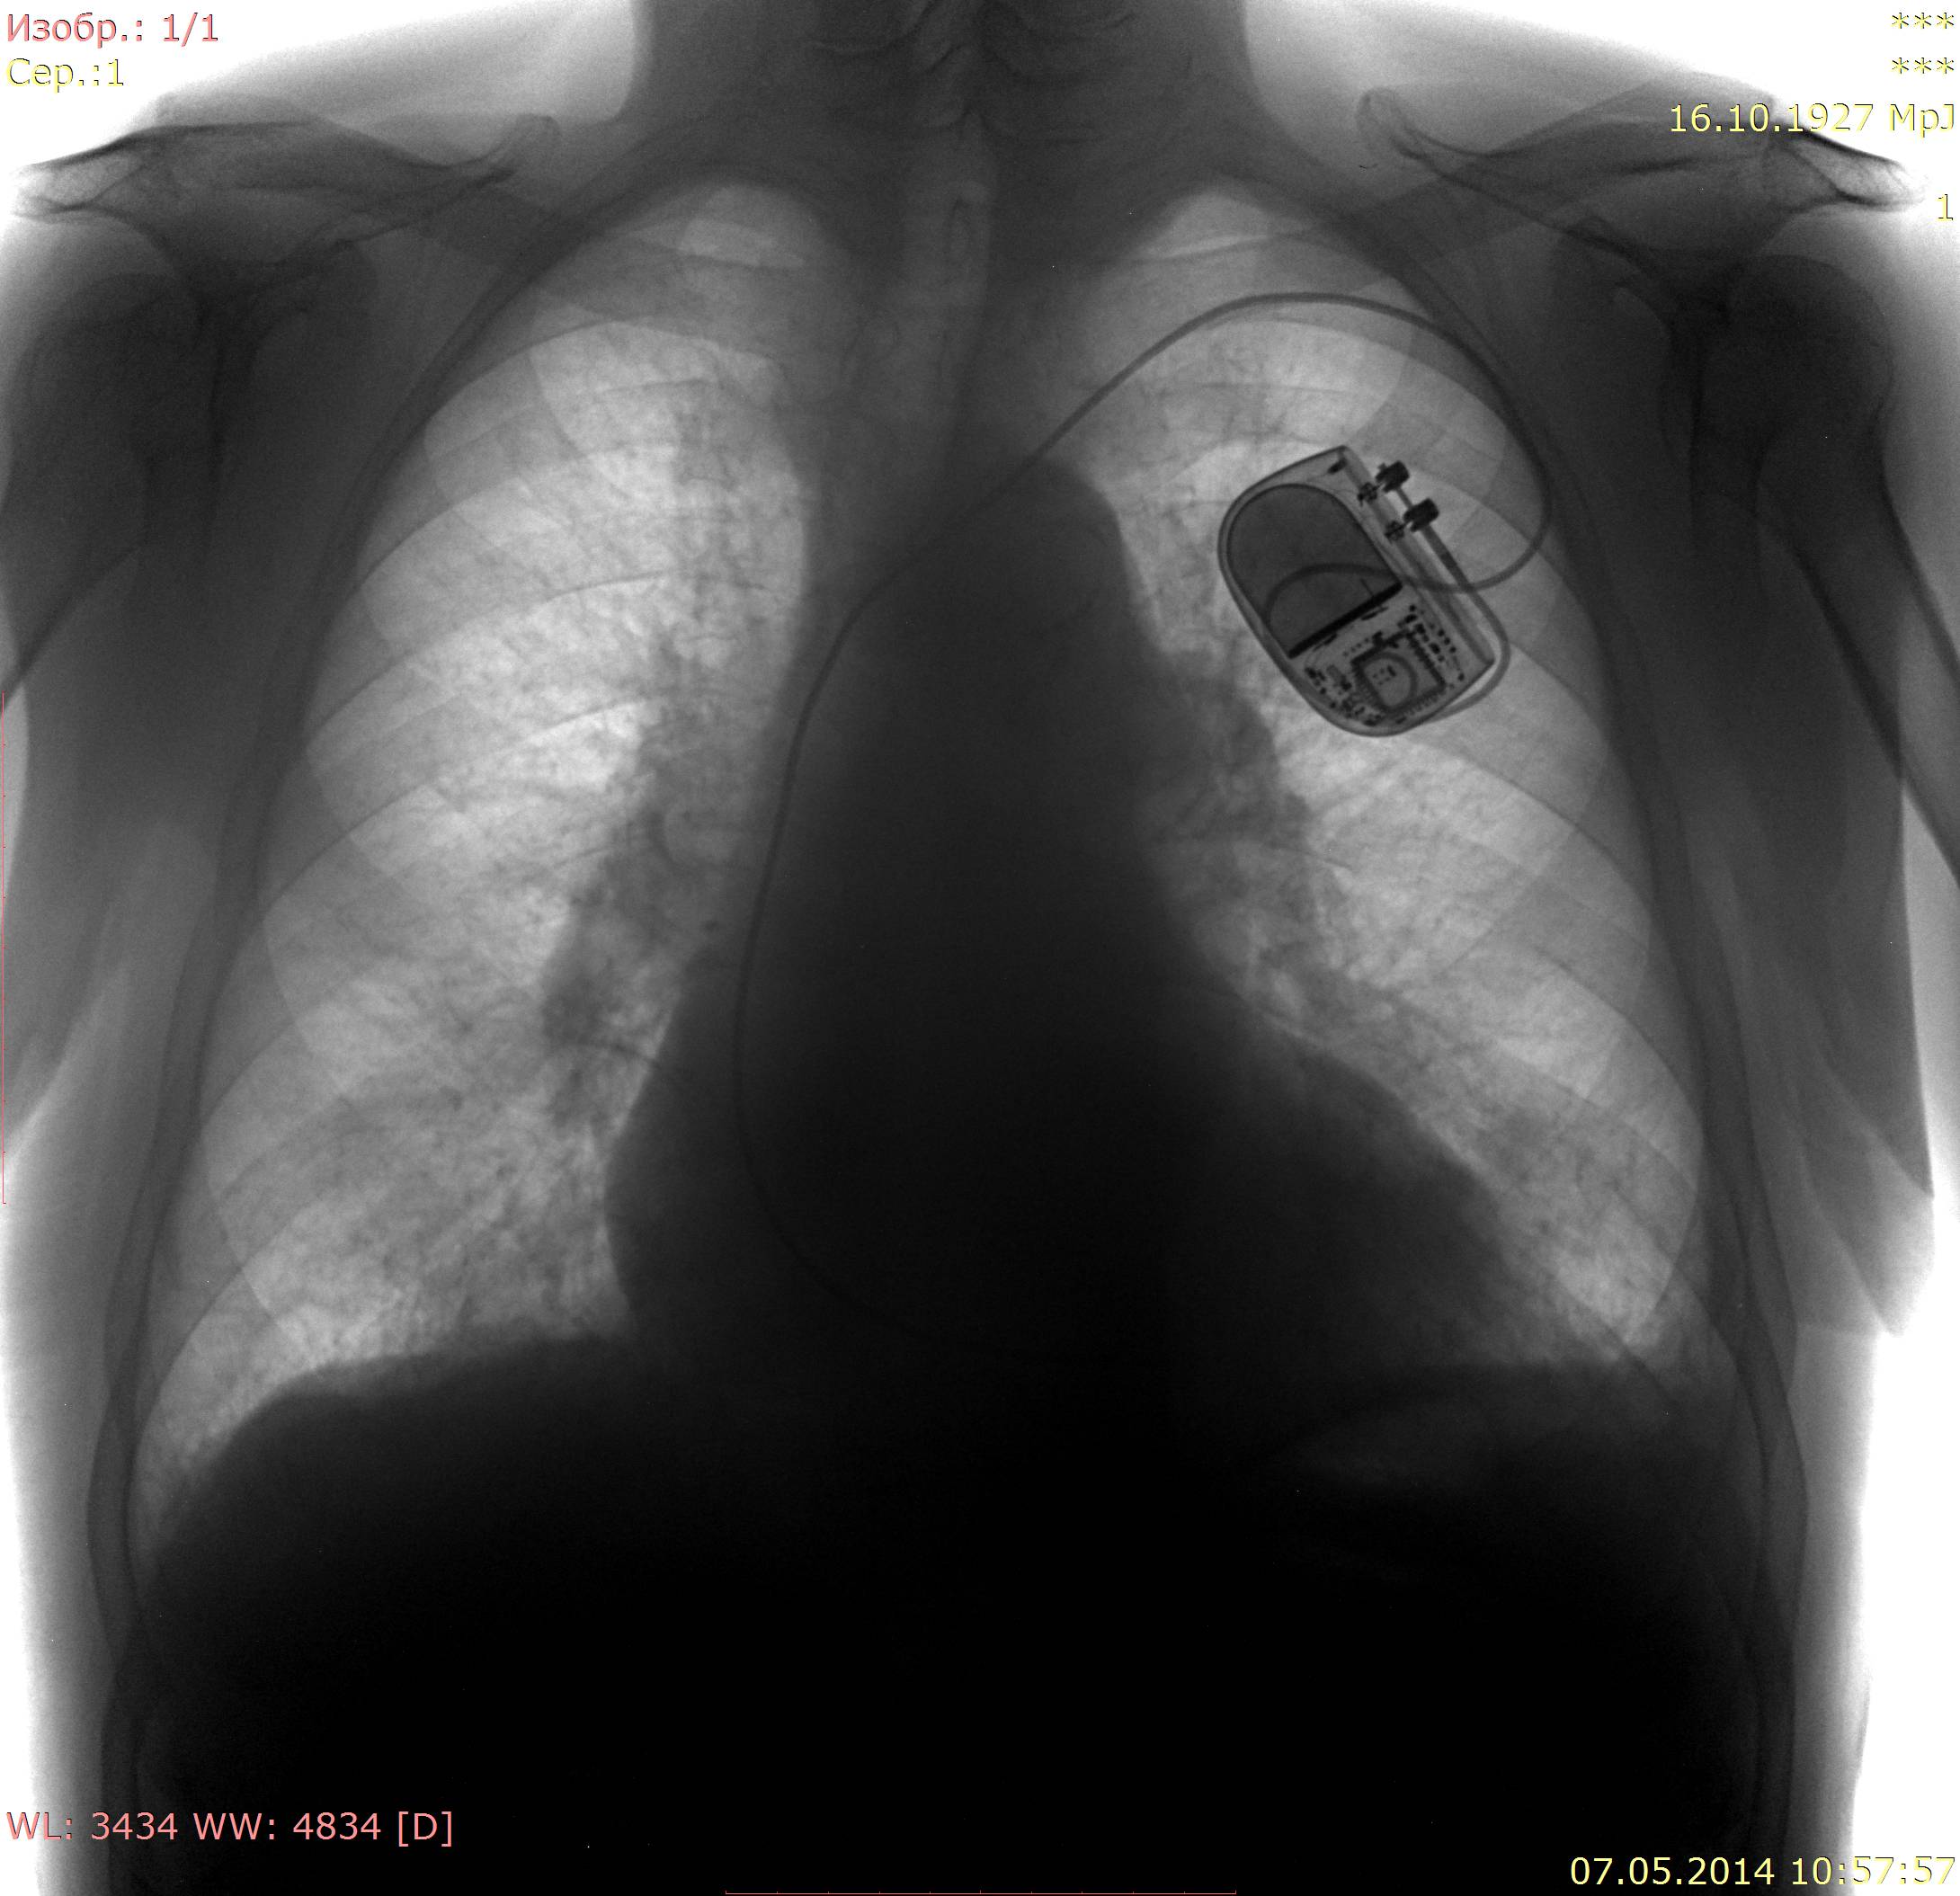

Поражение легких является одним из основных симптомов коронавируса (COVID-19). В данной статье представлены фото рентгеновских снимков, которые позволяют визуально оценить состояние легких при этом заболевании.

На фотографиях рентгеновских снимков видно, как вирус воздействует на легочную ткань. Характерные признаки поражения легких включают пятна, инфильтраты и наличие жидкости внутри легочных альвеол.

Фото рентгеновских снимков помогают врачам и специалистам визуально определить степень поражения легких и принять соответствующие меры лечения и поддержки пациента.